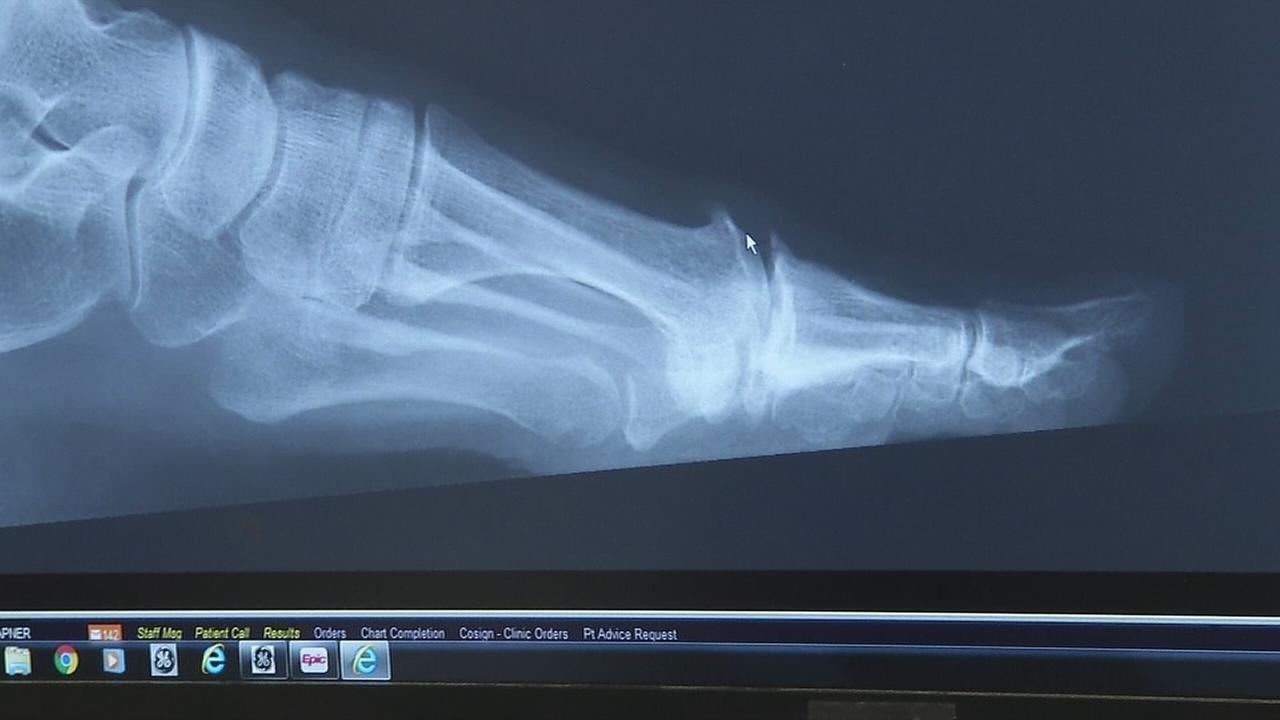

from www.drmikesmith.com.au

1st MTP Joint (Big Toe Joint) Fusion Dr Mike Smith Adelaide